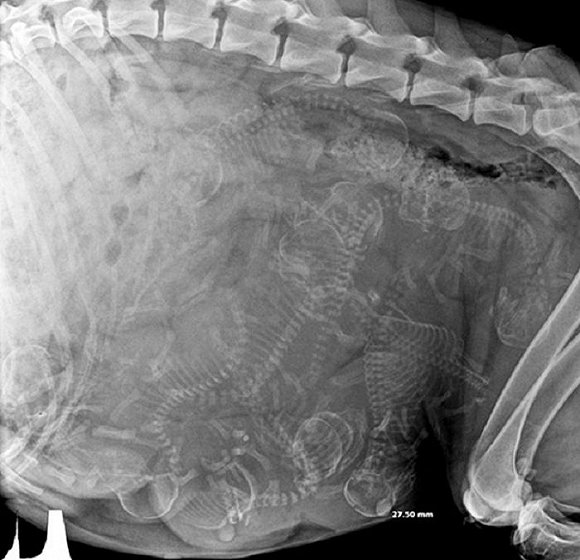

可爱又毛骨悚然 怀孕动物的X光片

人类之间分享母亲肚子里胎儿的X光片是一件非常常见的事情,但是,纵使你觉得自己对X光片已经见怪不怪,在看到了下面这些怀孕动物的X光片后你仍旧会说"哦我的天哪"。

自然总是充满有趣事实,你是否知道在各种怀孕的动物中负鼠的生育速度最快?它们只需要14天就可以分娩,而雌性大象的怀孕时间则长达23个月。现在 吉尼斯世界记录上记载的一次分娩中最大小狗出生数量为24只,而海马的生殖则由雄性负责,一只雄性海马每次平均产出200只幼鱼苗。

以下就是一些动物在怀孕时的X光片。

1. 乌龟